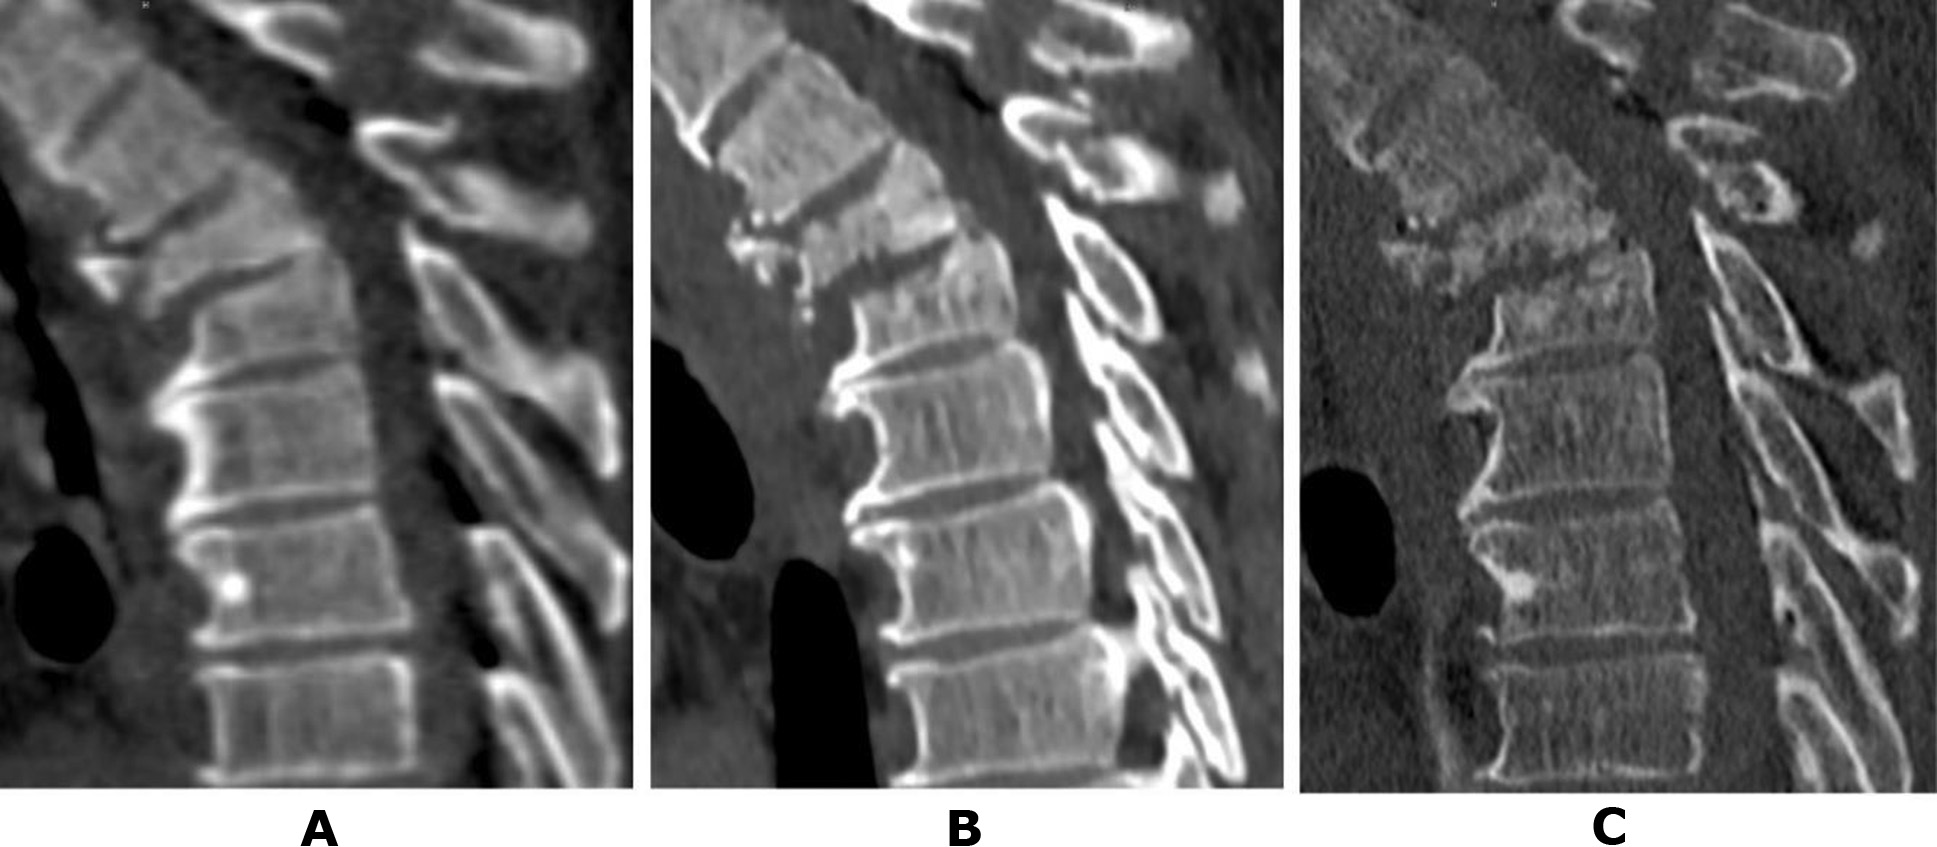

Patient N., a 50-year-old military serviceman, sustained injuries as a result of a road traffic accident (RTA) while driving. During initial hospitalisation at a military hospital, CT scans of the cervical, thoracic, and lumbar spine were performed. Diagnosed injuries included an incomplete burst fracture of the vertebral body and a comminuted fracture of the vertebral arch at Th3 (type B2), a compression fracture of Th4 (type A1), and a fracture of the spinous process of Th2 (Fig. 1A). The neurological status of the patient corresponded to ASIA E. Given the preserved neurological functions and certain technical challenges associated with performing stabilisation surgery, the patient was evacuated in stages and subsequently admitted to the Romodanov Institute of Neurosurgery, NAMS of Ukraine. CT scans conducted at each hospital allowed monitoring of the dynamic changes in the bony structures at the injury site. Two weeks post-injury (Fig. 1B), initial signs of lysis in the anterior sections of the Th3 vertebral body and erosion of the Th4 vertebral endplate were observed.

After one month (Fig. 1C), the anterior half of the Th3 vertebral body was fragmented into separate bone pieces, and pathological changes extended to the posterior part of the body. Negative changes were also noted in the Th4 vertebral body, though these were less pronounced.An analysis of the provided medical documentation revealed that C-reactive protein (CRP) levels post-injury did not exceed 4.8 mg/L, and peripheral blood leukocytes remained at 7.6 × 10¹²/L, ruling out a septic nature for the observed changes [19–21].

Fig. 1. Patient N., 50 years old. CT scans of the thoracic spine: A – on the day of the injury; B – after 2 weeks; C – after 1 month (details in the text)